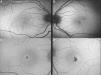

MethodsA retrospective study was conducted on the 12 eyes of 6 patients with MacTel 2. Fundus color photographs, fundus autofluorescence, fluorescein angiography, optical coherence tomography (OCT), and OCT-angiography were performed and subsequently analyzed. Visual acuity (VA) was prospectively recorded. The prevalence was established based on the patients referred to a specialized macular diseases unit. Minimum follow-up period was 18 months.

ResultsPrevalence of MacTel 2 in our study was 0.12%. Clinical features were presented using multimodal retinal imaging. VA remained stable during follow-up. Three patients developed choroidal neovascularisation (CNV), requiring intravitreal treatment with antiangiogenic agents.